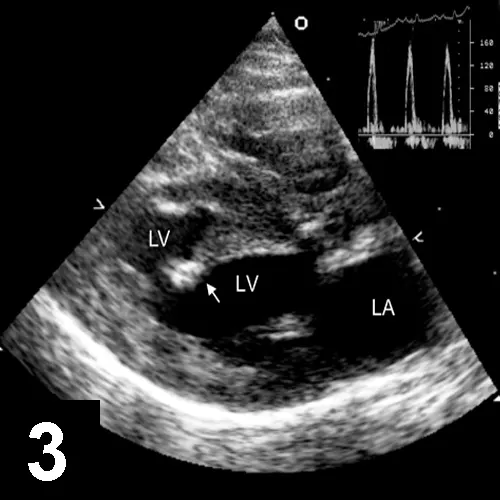

DEFINITIVE DIAGNOSISAn echocardiogram (see Figure 3 below) obtained 3 days after presentation demonstrated moderate to severe atrial enlargement, normal to mild left ventricular wall thickening, a normal left ventricular chamber, and a fibrous/fibromuscular band of tissue traversing the left ventricular lumen (see Echocardiogram Summary).

Figure 3. Right parasternal long-axis echocardiogram showing the left atrium (LA) revealed a fibrous band of tissue (arrow) spanning the LV cavity. The inset shows a spectral pulsed-Doppler tracing of transmitral inflow.

Doppler study of the diastolic mitral inflow revealed an elevated E:A ratio (between early and late ventricular mitral filling velocity), rapid deceleration time of the E-wave, and elevated mitral inflow velocity in the absence of significant mitral regurgitation. No blood flow gradient across the fibrous LV band was detected. These findings are most consistent with restrictive-type cardiomyopathy.

• The echocardiogram revealed a band of fibrous (or fibromuscular) tissue that spanned the left ventricular lumen, normal to mildly thickened left ventricular walls, and moderate to severe left atrial enlargement. Blood flow from the left atrium to the left ventricle was increased in velocity, which is consistent with altered left ventricular diastolic function and elevated left atrial pressure (ie, restrictive filling pattern). Although the echocardiogram provided a definitive diagnosis, depending on the history, clinical signs, as well as examination, ECG, and radiographic findings, echocardiography is not always necessary before initiation of therapy. Thus, the lack of immediate access to echocardiography does not automatically preclude the detection and initial treatment of congestive heart failure in cats.